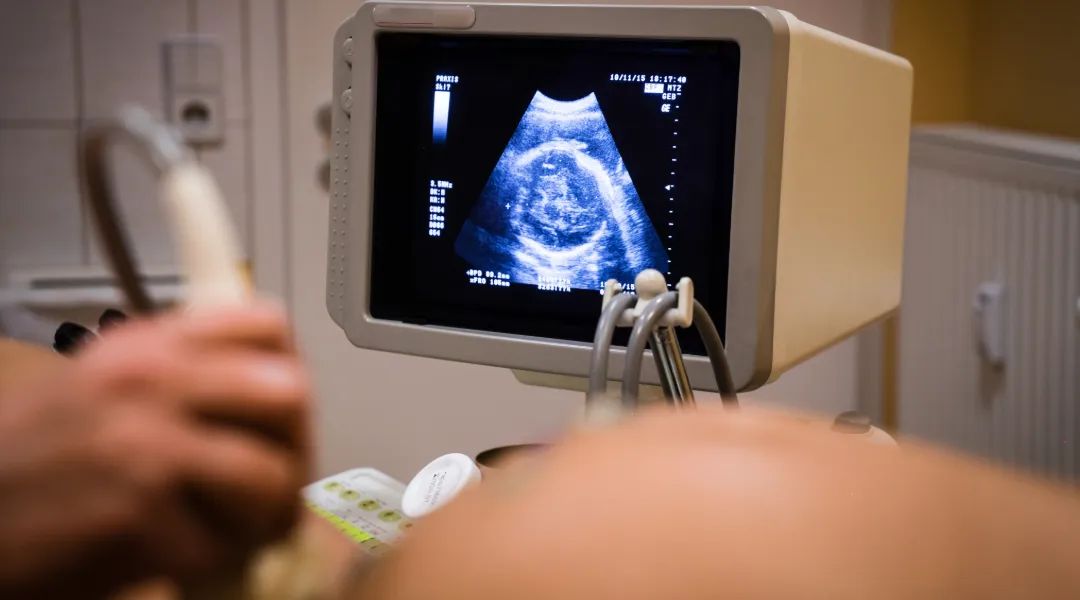

The 20-week ultrasound visit is always an exciting moment for new parents. That’s when parents usually find out if they’re having a boy or girl. But parents should know there’s far more to the 20-week ultrasound than helping them decide the color of the gender-reveal cake.

“It’s the time you figure out the sex of the fetus, but it’s the time we are really looking at all of the organs and anatomy to make sure everything looks like it should,” said Erica Smith, Maternal Fetal Medicine specialist with Intermountain Health and St. Vincent Regional Hospital.

Moms and dads can ask about the images of their baby’s heart, brain and kidneys and it’s a good idea to ask your prenatal care provider:

- “Did the sonogram show everything you needed it to?”

- “Could you rule out problems the baby could be born with?”

- “Did they get images to help make sure my baby’s heart, brain and kidneys are developing normally?”

If the answer is no or inconclusive, ask what next steps to take to ensure the baby’s organs can be viewed appropriately.

If something is found to be wrong with the baby’s heart, for example, your care team will help you make a plan to ensure the baby gets the best care during pregnancy and right after birth.

“Knowing about your baby’s heart condition early really helps you plan to provide the best care for your baby right after the birth instead of waiting for your baby to display symptoms,” said Smith.

If parents are told to return for more imaging, it doesn’t necessarily mean something’s wrong.

“Being told to come back for more imaging can be anxiety-provoking and nerve-wracking, but often it’s because the pictures from the ultrasound weren’t clear enough. Until someone tells you something definitive, try not to worry,” said Smith.

Fetal heart specialists say most of the time when moms need a fetal echocardiogram, there are no problems detected.